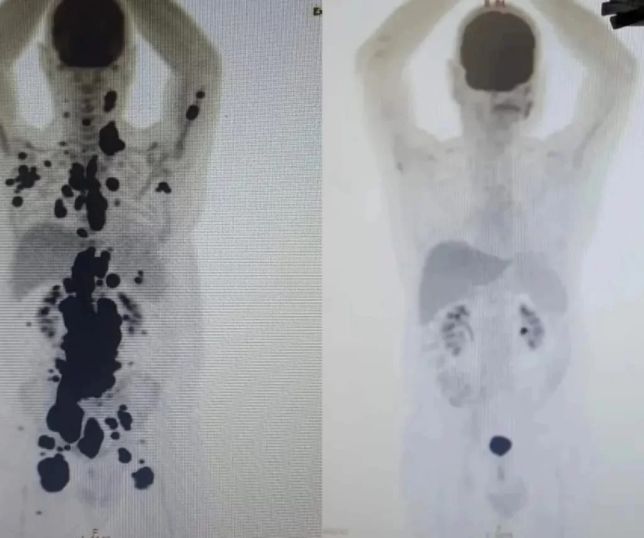

.jpeg)

Fotos: Reprodução